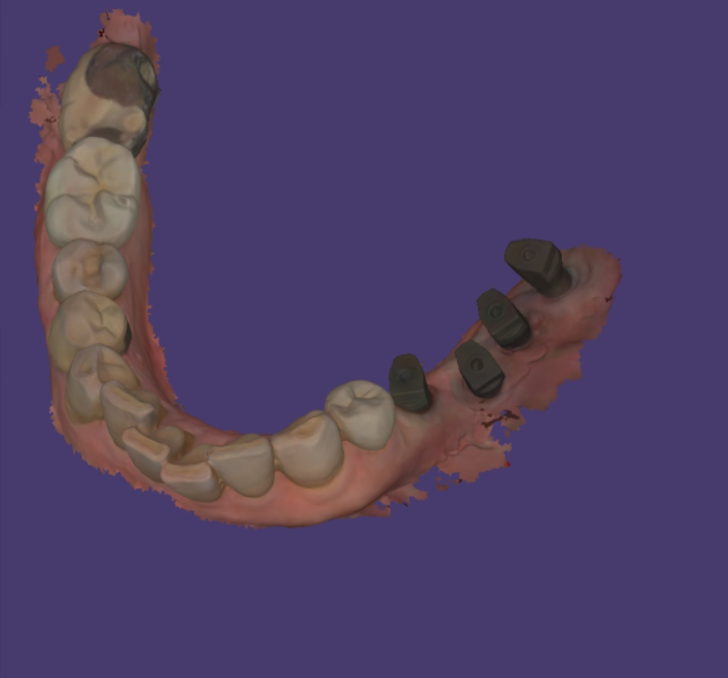

디지털 스캐너를 사용하여

뽄을 뜨고

보철 작업을 하고 있는데 말이죠

왼쪽 아래 임플란트 수술을 끝내놓고

보철을 만들쯔음

사건이 생겼습니다.